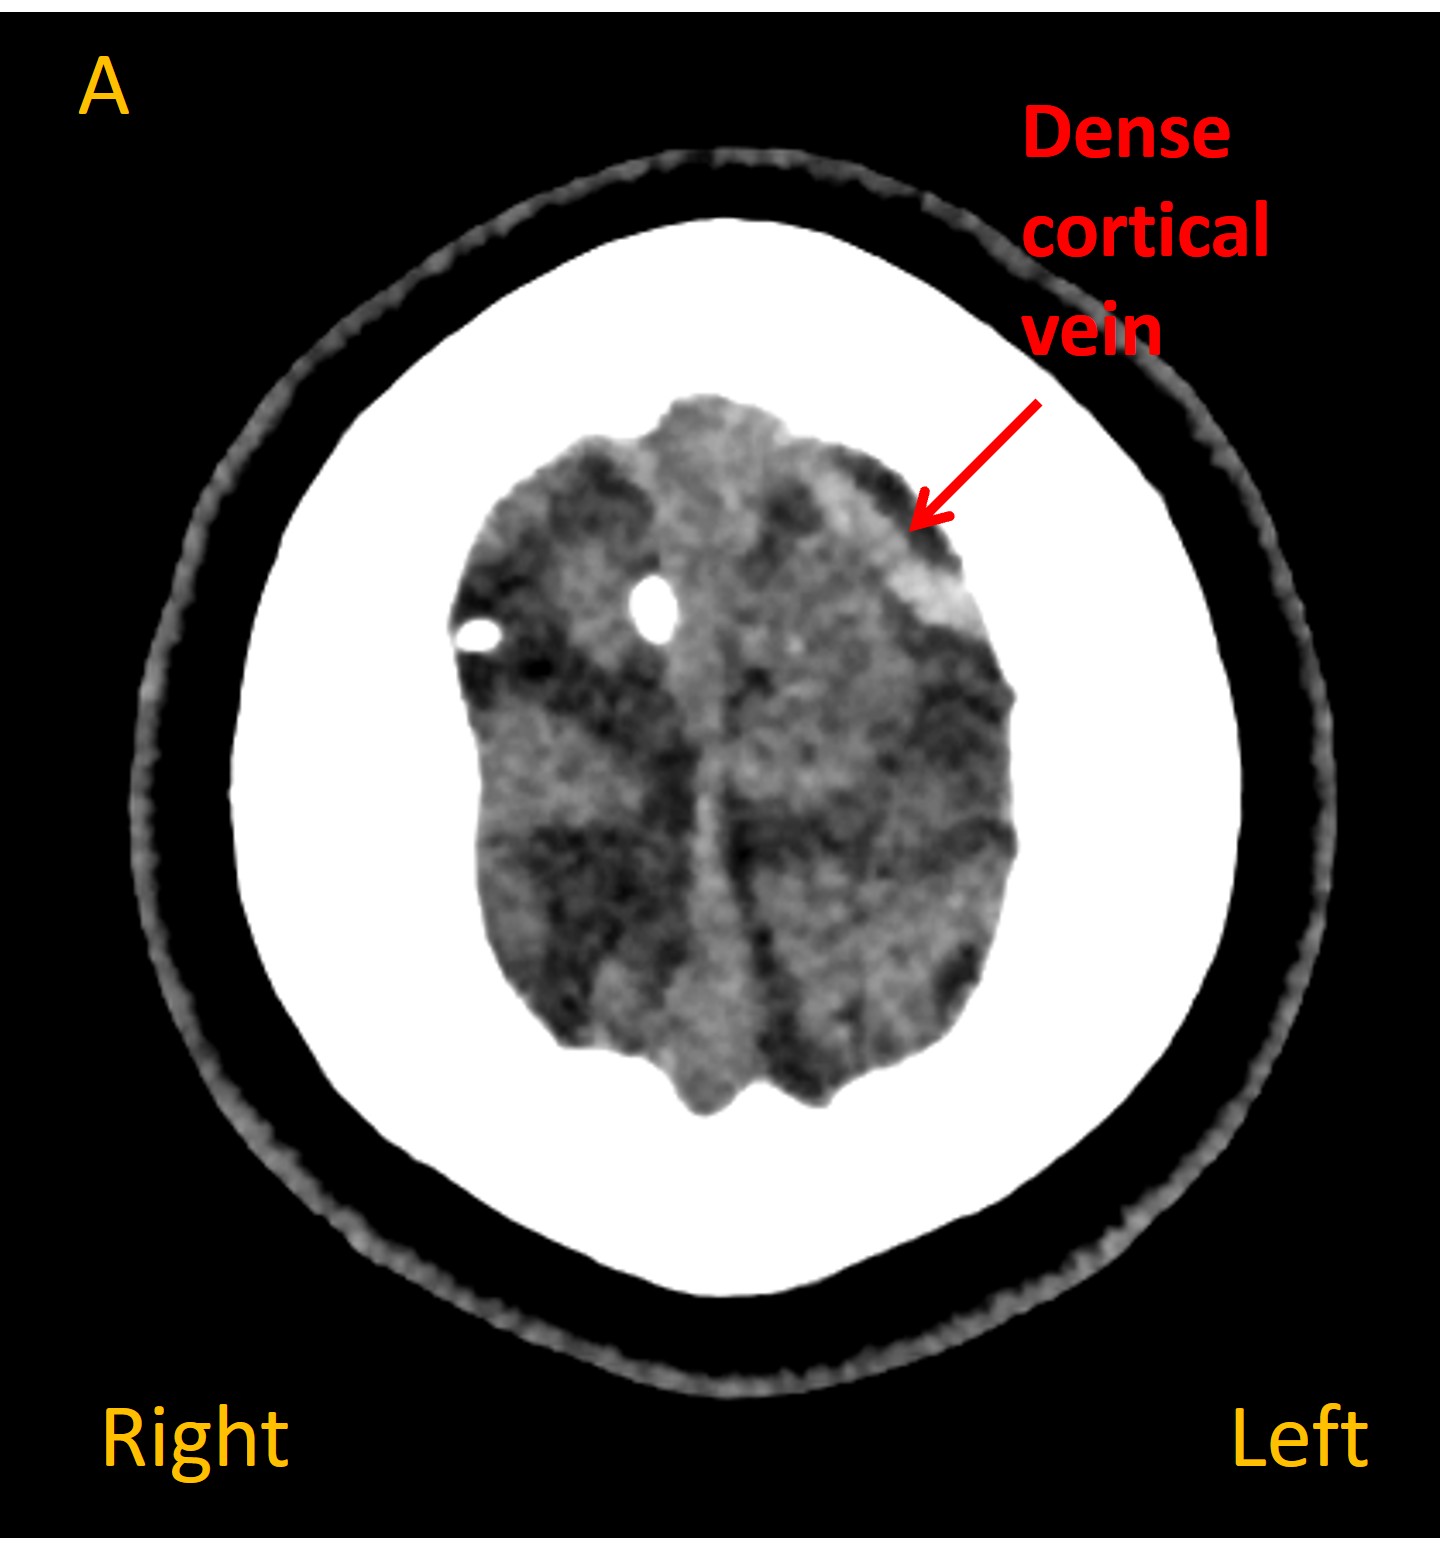

On a plain CT head a dense cortical vein was visible overlying the left frontal lobe, suggestive of static blood ( Images A and B ). A dark area of hypoattenuation was visible in the underlying brain, suggesting a venous infarction (C). Contrast venography identified a filling defect in the vein - confirming cortical venous thrombosis ( D ).